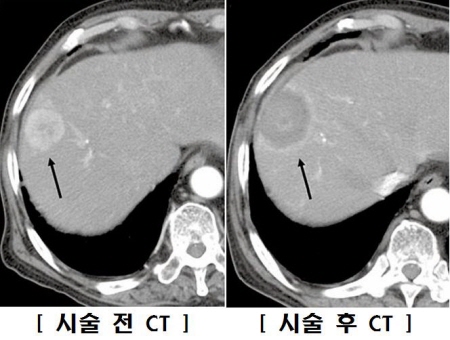

국소치료술로는 초음파 등의 영상검사로 종양의 위치를 파악한 후 전류가 흐르는 바늘을 찔러 넣고 열을 가해 종양을 괴사시키는 고주파열치료술(radiofrequency ablation, RFA)과, 전류 대신 에탄올을 넣어 치료하는 경피적에탄올주입술(percutaneous ethanol injection therapy, PEIT)이 있습니다. ‘경피적(經皮的)’이란 피부에 바늘을 찔러 넣어 목표물에 접근한다는 뜻입니다. 이러한 요법들은 종양이 하나만 있고 5cm 이하이거나, 3개 이하이면서 모두 3cm 이하일 경우에 주로 시행됩니다. 작은 간암의 치료에서는 수술에 필적하는 좋은 결과를 낼 수 있어서 널리 쓰입니다.

크기가 2cm 이하인 종양에서는 이들 두 치료법의 결과에 큰 차이가 없지만, 2cm 이상인 종양에는 에탄올주입술보다 고주파 치료술이 효과가 큰 것으로 알려졌습니다. 그러나 고주파열치료술은 에탄올주입술에 비해 시술 후 합병증이 좀 더 많고, 종양 주위에 혈관이 있거나 종양의 위치가 대장‧담낭 등 다른 장기에 인접한 경우에는 효과적으로 치료하기가 어렵다는 단점이 있습니다.

고주파 열치료술 시술 전후의 간암 비교(CT 영상) 이미지

[고주파 열치료술 시술 전후의 간암 비교(CT 영상)]